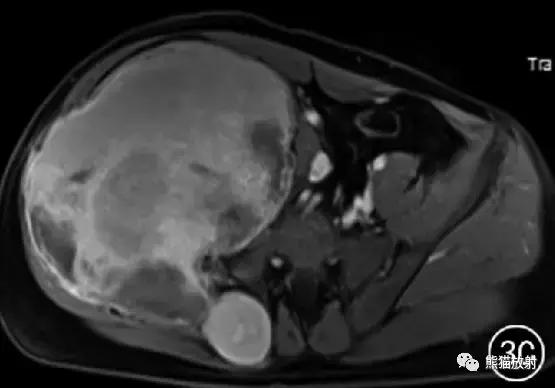

图3 男38岁。右侧髂骨骨内型假肿瘤。右侧髂骨区见巨大肿块,同髂骨翼骨质膨胀性破坏,邻近臀肌、髂腰肌及盆腔内组织受压移位,T1WI呈高、低混杂信号(A) ; 增强扫描未见强化。